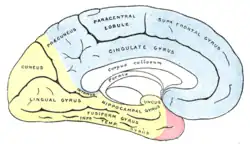

Медиальная поверхность больших полушарий головного мозга, показывающая области, кровоснабжаемые теми или иными мозговыми артериями. Области, кровоснабжаемые задней мозговой артерией, показаны жёлтым цветом.

Медиальная поверхность больших полушарий головного мозга, показывающая области, кровоснабжаемые теми или иными мозговыми артериями. Области, кровоснабжаемые задней мозговой артерией, показаны жёлтым цветом. Артерии головного мозга, вид со стороны основания мозга (снизу). Задняя мозговая артерия, составляющая часть Виллизиева круга, отмечена вблизи центра изображения. С правой стороны удалена часть височной доли коры больших полушарий головного мозга, а также часть правого полушария мозжечка.